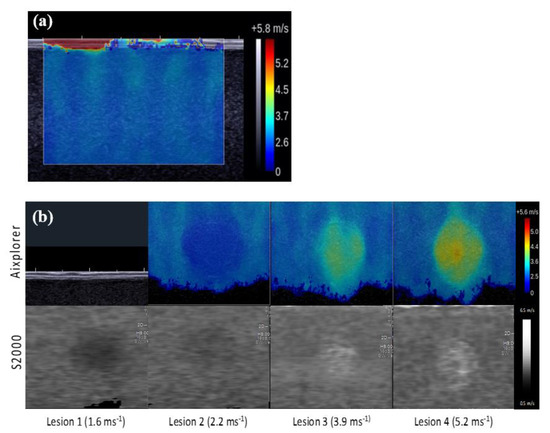

3.1. Difference in cs Estimates between Machines In Vitro

4.1. Difference in cs Estimates between Machines In Vitro

| Background | Inclusion 1 | Inclusion 2 | Inclusion 3 | Inclusion 4 | Mean (SD) | |

|---|---|---|---|---|---|---|

| Nominal cs | 2.90 | 1.60 | 2.20 | 3.90 | 5.20 | |

| Aixplorer: cs estimates (ms−1) | ||||||

| Observer 1 | 2.50 | 2.00 | 2.60 | 3.80 | 4.10 | |

| Observer 2 | 2.60 | 1.90 | 2.50 | 3.70 | 4.30 | |

| Observer 3 | 2.50 | 1.80 | 2.50 | 3.60 | 4.10 | |

| Mean | 2.53 | 1.90 | 2.53 | 3.70 | 4.17 | |

| CV | 0.02 | 0.05 | 0.02 | 0.03 | 0.03 | |

| S2000: cs estimates (ms−1) | ||||||

| Observer 1 | 2.55 | 1.78 | 2.50 | 3.51 | 4.17 | |

| Observer 2 | 2.47 | 1.89 | 2.40 | 3.40 | 4.11 | |

| Observer 3 | 2.55 | 1.90 | 2.49 | 3.53 | 4.11 | |

| Mean | 2.50 | 1.90 | 2.50 | 3.50 | 4.10 | |

| CV | 0.02 | 0.04 | 0.02 | 0.02 | 0.01 | |

| Symmetric percentage differences in cs estimates (%) | ||||||

| Observer 1 | −0.99 | 5.82 | 1.96 | 3.97 | −0.85 | 1.98 (2.98) |

| Observer 2 | 2.56 | 0.26 | 2.04 | 4.23 | 2.26 | 2.27 (1.41) |

| Observer 3 | −0.99 | −2.70 | 0.20 | 0.98 | −0.12 | −0.53 (1.41) |

| Mean | 0.20 | 1.15 | 1.40 | 3.06 | 0.44 | 1.25 (1.12) |